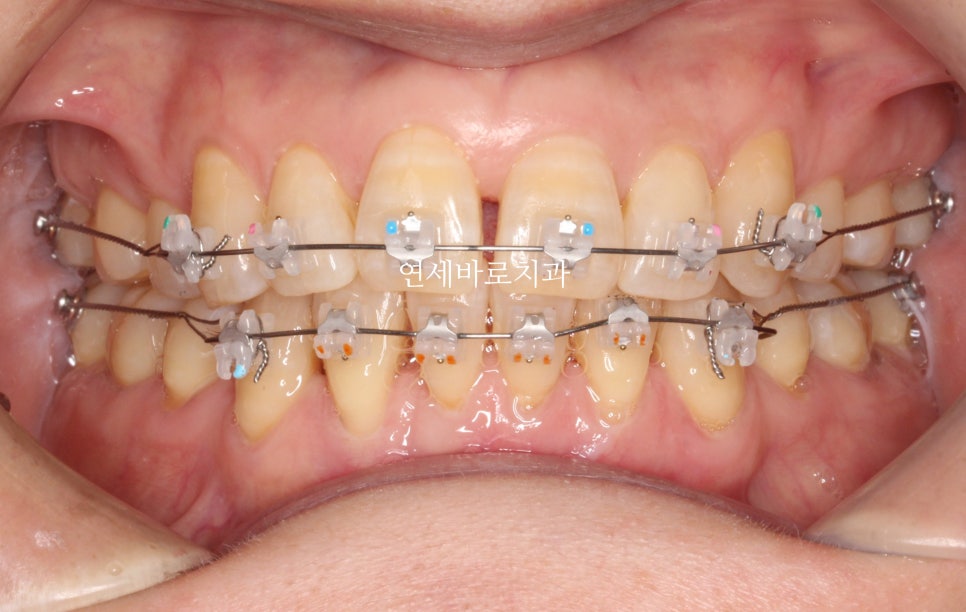

1) 어금니쪽 교정장치는 어디회사 제품을 사용하나요?

2) 와이어는 어디회사 제품인가요?

3) 파워체인은 어디회사 제품인가요?

하지만 안보이는 것들이 더 중요한 것이 교정치료입니다.

특히 와이어와 파워체인은 너무나도 중요합니다.

저가의 중국산 와이어와 파워체인은 제가 사용하는 것에 비하면 거의 1/10 또는 그 이하의 가격입니다.

그걸로 교정치료를 하면 치료기간이 매우 길어집니다.

그리고 치근 흡수 등 다양한 부작용이 잘 생깁니다.